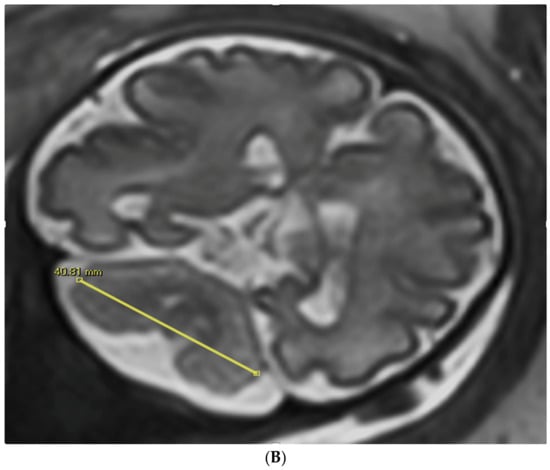

Figure 1.

TCD measured in an image by trans-abdominal axial US scan at 31 weeks of gestation (A) and by coronal MRI scan at 32 weeks of gestation (B).